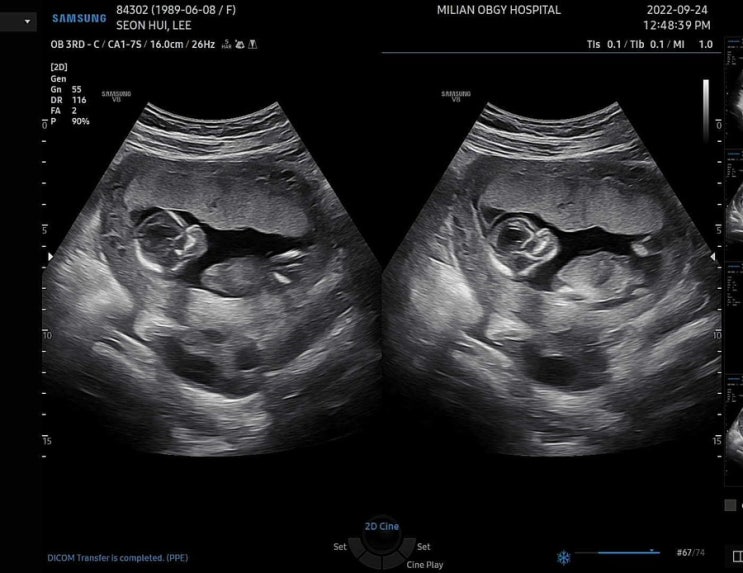

17주 4일 초음파 보고오기

오늘 17주 4일, 병원다녀온지 14일째에 잘있는지 궁금해서 못참겠어서 병원에 다녀왔다. 오늘 아침엔 배도 ...

임신 14주 5일 궁금해서 못참고 병원행

투헤헤헤 이렇게 많이컸다니 ㅠㅠ 어제 밤에 잘때 왼쪽아래에서 꿀렁이 한번 느껴지고 오늘 가보니 딱 그위...